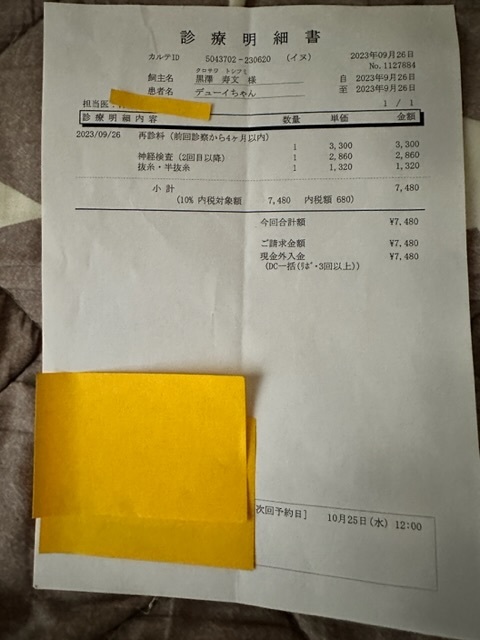

術後2週間経過後、抜糸

手術後も暫くは通院が必要とのことです。

クラウドファンディング目標金額690.000円

実施済みの外科的手術や皮膚トラブルによる

通院、検査、手術費用など

477.866円

※上記は大学病院で頂いた診断書

※下記は初診かつ、会陰形成術をして頂く動物病院より発行して頂いた診断書、治療計画書

実際にかかった治療費

術後抜糸